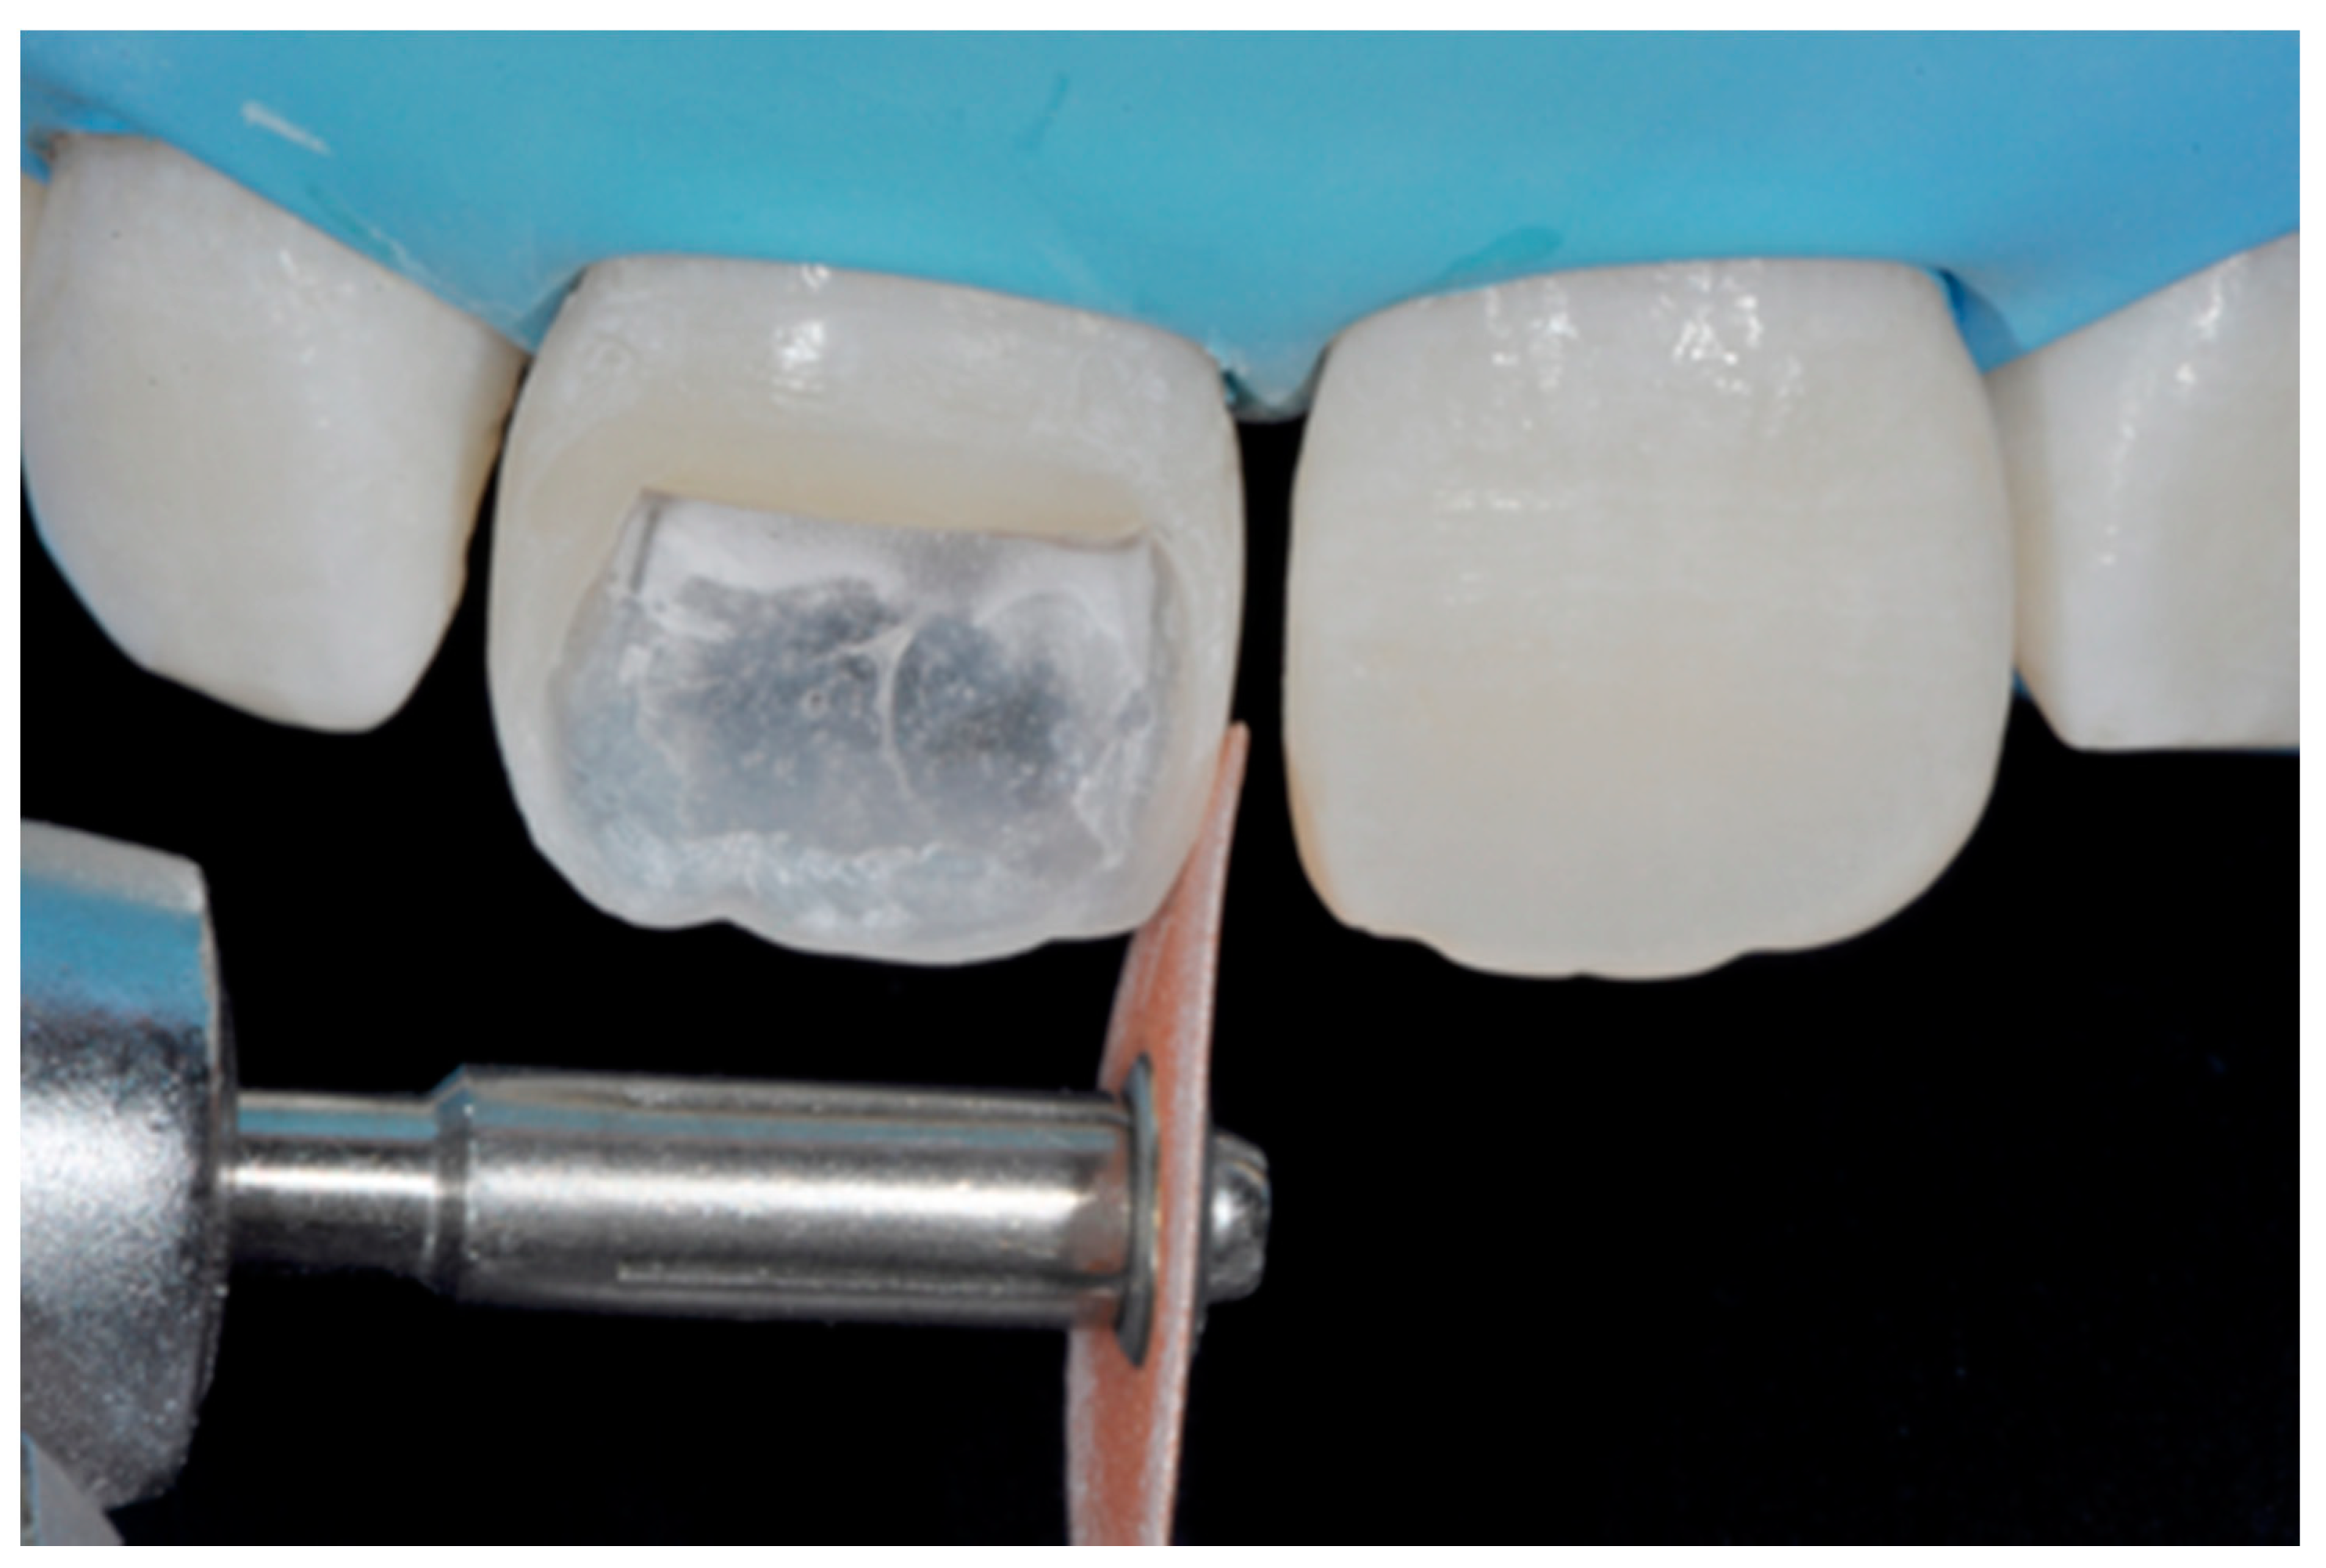

The internal ones can be reduced with diamond burs (WL 268 014 Horico, Berlin, Germany) (Figure 8).

Figure 8.

Excessive thickness of interproximal walls is reduced with a low-speed diamond bur. Reprinted from Restauri diretti nei settori anteriori, G. Paolone, S. Scolavino, © 2021, with permission from Quintessence Publishing Italy.

Step 3 (adhesive procedure): After frame modification, dust was removed with strong air pressure and internal surface was treated with a silane coupling agent (Monobond Plus, Ivoclar Vivadent, Schaan, Liechtenstein) applied with a microbrush in a thin layer and allowed to react for 60 s. An adhesive (OptiBond FL, Kerr, Bioggio, Switzerland) was applied following manufacturer’s instructions, and photoactivated for 20 s (Figure 9).

Figure 9.

After frame modification silane coupling agent and adhesive procedures are applied. Reprinted from Restauri diretti nei settori anteriori, G. Paolone, S. Scolavino, © 2021, with permission from Quintessence Publishing Italy.